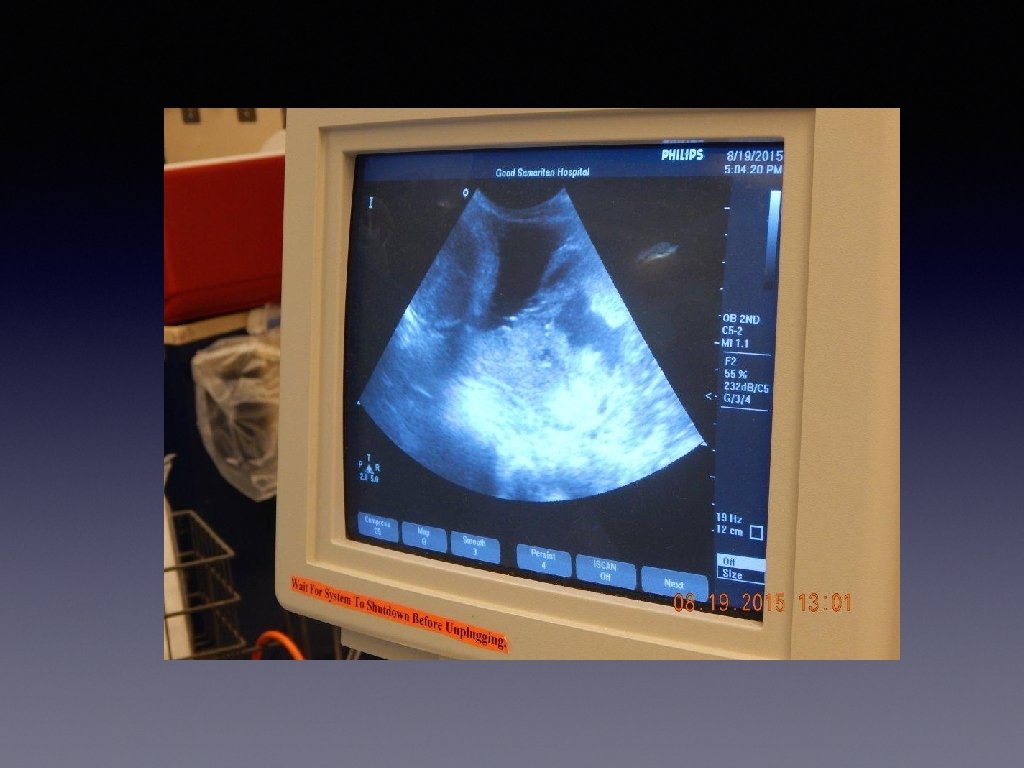

Prenatal Diagnosis • When the diagnosis is made it is usually made by ultrasound in the second or third trimester. • Sonographic findings suggestive are • • loss of normal hypoechoic retroplacental zone • multiple vascular lacunae (irregular vascular spaces) within the placenta “swiss cheese” appearance • blood vessels or placental tissue bridging the uterine-placental margin, myometrialbladder interface, or crossing uterine serosa • retroplacental myometrial thickness < 1 mm • numerous coherent vessels visualized with 3 -D color/power Doppler in a basal view. If sonographic findings are inconclusive or a placenta percreta is suspected, MRI may be useful.

Ultrasound Findings Suggesting Morbidly Adherent Placenta First trimester • • Gestational sac that is located in the lower uterine segment • Multiple irregular vascular spaces noted within the placental bed • Implantation of gestational sac imbedded into cesarean delivery sac (“cesarean scar ectopic”) Second trimester • • Multiple vascular lacunae within placenta

Ultrasound Findings Suggesting Morbidly Adherent Placenta • Third trimester • Loss of normal hypoechoic retroplacental zone • Presence of multiple vascular lacunae within placenta (Swiss-cheese appearance) • Abnormalities of uterine serosa-bladder interface (intertuption of line, thickening of line, irregularity of line, and increased vascularity • Extension of villi into myometrium, series, or bladder • Retro-placental myometrial thickness of< 1 mm • Turbulent blood flow through lacunae on Doppler ultrasonography • Increased subplacental vascularity • Vessels bridging form placenta to uterine margin • Gaps in myometrial blood flow